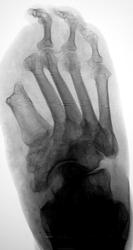

Пол пациента: Женский пол Тип патологии: Другое Область исследования: Скелетно-мышечная система Методы исследования: Rg Пациент направлен на рентгенографию стопы. https://radiomed.ru/sites/default/files/styles/case_slider_image/public/user/12/2.dscn0864.jpg?itok=uzT7C77w ID:25515 Чт, 10/01/2013 - 22:56 #1 Наталия Васильевна Не на сайте Был на сайте: 5 лет 10 месяцев назад Зарегистрирован: 25.09.2011 - 09:02 Публикации: 754 Диабетическая стопа? Состояние после ампутации 1-2 пальцев, остеомиелит с разрушением костей предплюсны. А что в анамнезе? Чт, 10/01/2013 - 23:15 #2 Катенёв Валенти... Не на сайте Был на сайте: 7 лет 2 месяцев назад Зарегистрирован: 22.03.2008 - 22:15 Публикации: 54876 В анамнезе диабет. Пт, 11/01/2013 - 12:14 #3 Popovpavel Не на сайте Был на сайте: 7 лет 4 месяцев назад Зарегистрирован: 08.06.2009 - 00:23 Публикации: 649 Мощный лизис. Пт, 11/01/2013 - 19:03 #4 Наталия Васильевна Не на сайте Был на сайте: 5 лет 10 месяцев назад Зарегистрирован: 25.09.2011 - 09:02 Публикации: 754 А дальше-выше, выше и выше. Очень неблагодарное лечение.

Диабетическая стопа? Состояние после ампутации 1-2 пальцев, остеомиелит с разрушением костей предплюсны. А что в анамнезе?

В анамнезе диабет.

Мощный лизис.